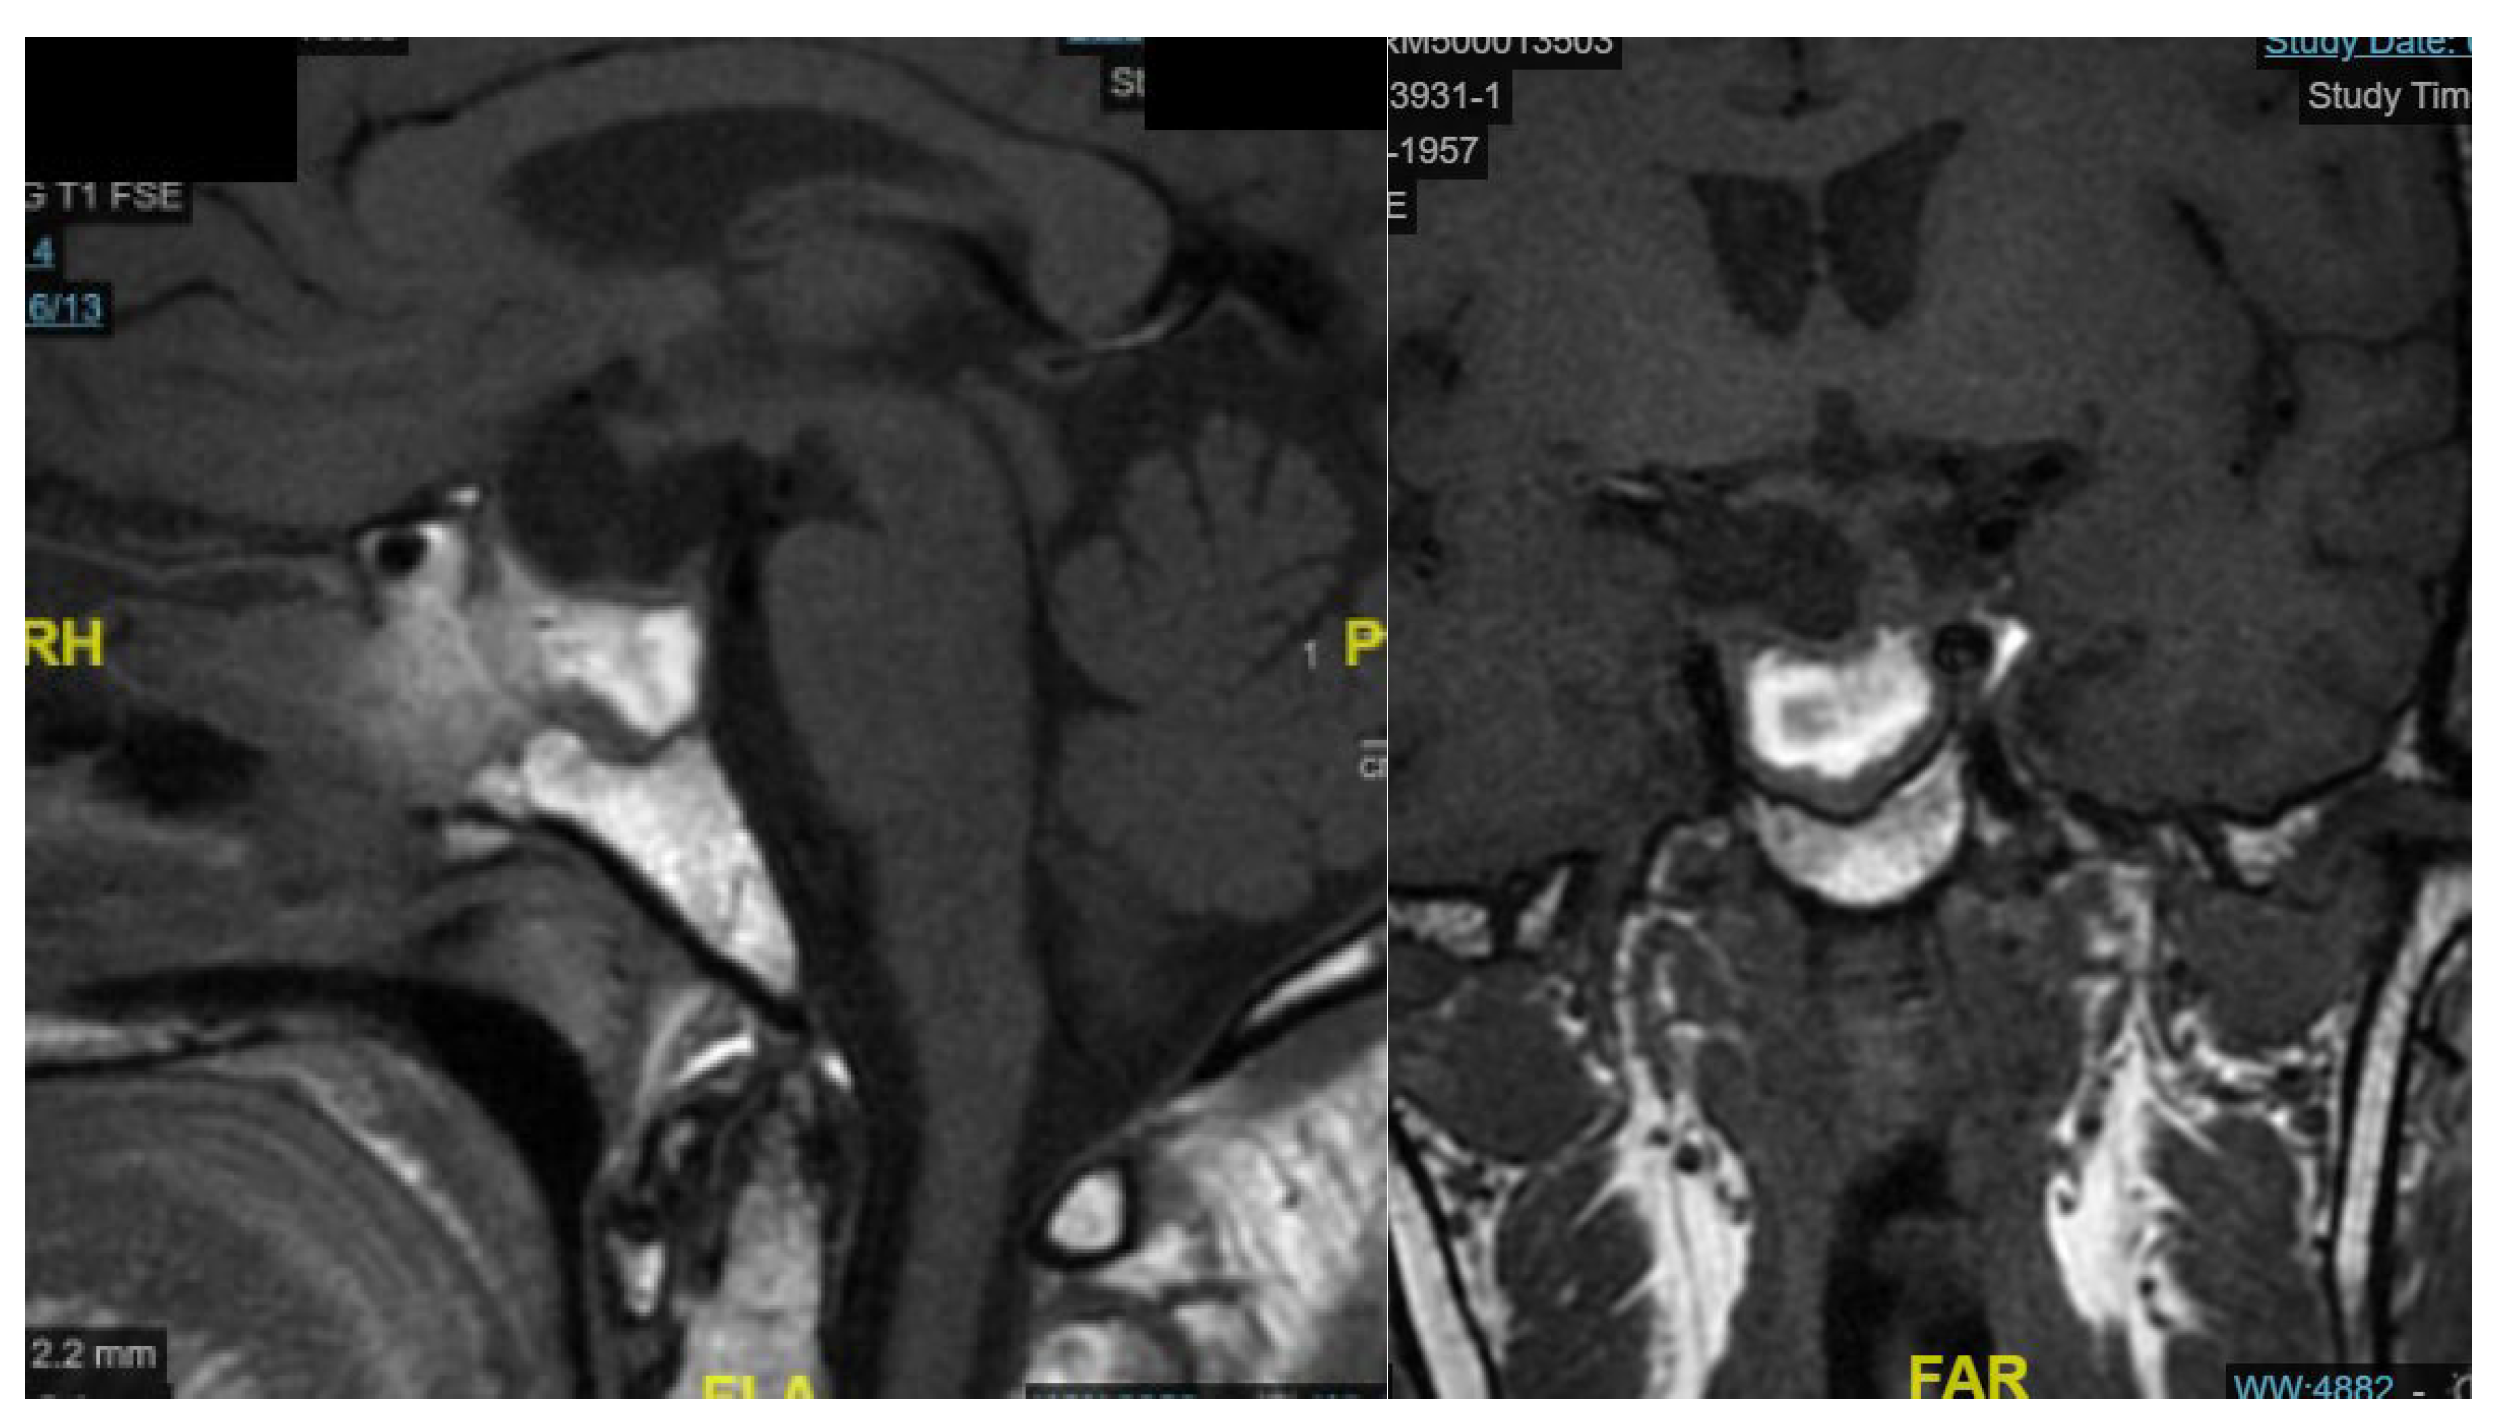

The patient showed significant clinical improvement, with resolution of visual symptoms and normalization of serum sodium levels. No postoperative cerebrospinal fluid leakage, nasal crusting, or olfactory dysfunction was observed. The MRI examination performed one month later shows packing material with no radiological evidence of residual lesion.

Figure 7. sagittal and coronal MRI one month after surgery.